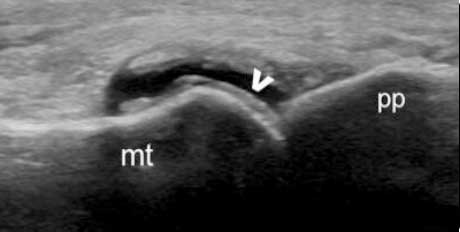

“˫����”

��ֺ�ؽ����DZ���ɼ�������������ǿ�����ǻ�Ĥ��Ե�ߣ���“˫����”��

������

���DZ��������ǿ��������Ĺ��Թؽ���ǿ�������γ�“˫����”��

�ۼ���

�����ǵ�˫����״����ʾ�����ڲ��ľۼ���